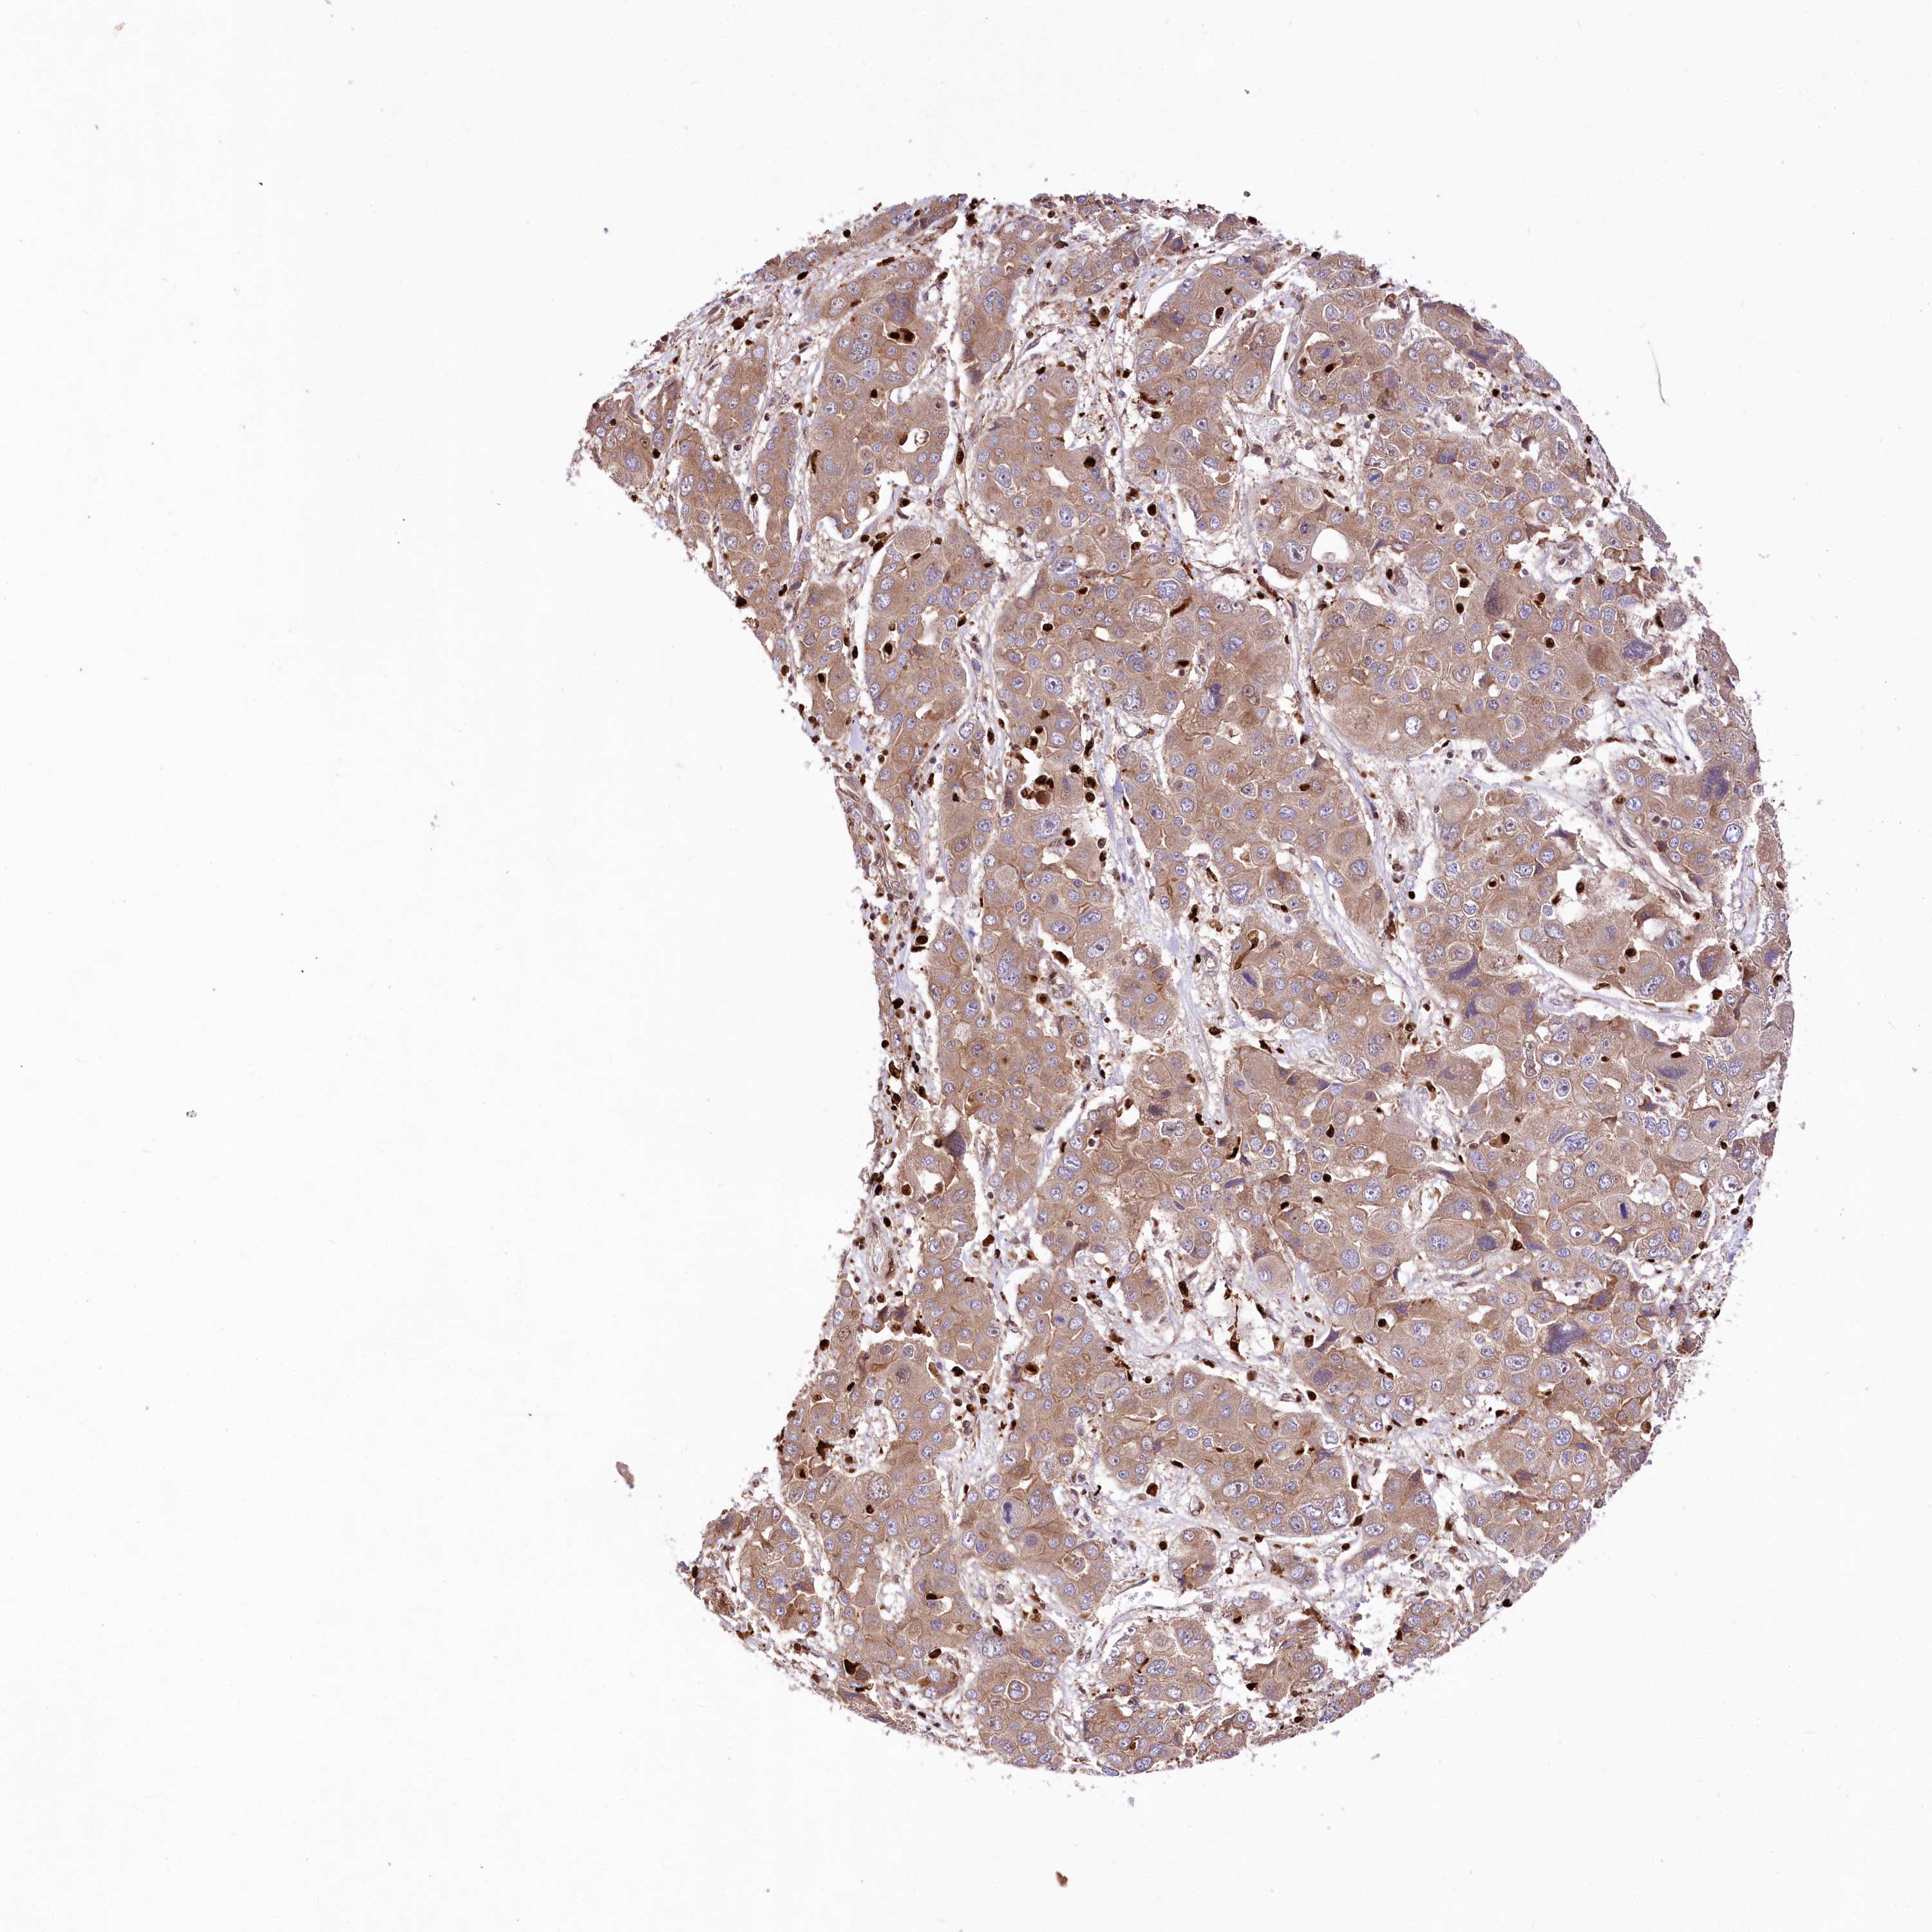

LIVER CANCER - Protein expressioni

A mouse-over function shows sample information and annotation data. Click on an image to view it in a full screen mode. Samples can be filtered based on level of antibody staining by selecting one or several of the following categories: high, medium, low and not detected. The assay and annotation is described here.

Note that samples used for immunohistochemistry by the Human Protein Atlas do not correspond to samples in the TCGA dataset.

Antibody stainingi

Antibody staining in the annotated cell types in the current human tissue is reported as not detected, low, medium, or high, based on conventional immunohistochemistry profiling in selected tissues. This score is based on the combination of the staining intensity and fraction of stained cells.

Each image is clickable and will lead to virtual microscopy that enables deeper exploration of all samples and also displays staining intensity scores, fraction scores and subcellular localization as well as patient and tissue information for each sample.

Antibody HPA034987

Staining

High

Medium

Low

Not detected

Intensity

Strong

Moderate

Weak

Negative

Quantity

>75%

75%-25%

<25%

None

Location

Nuclear

Cytoplasmic/membranous

Cytoplasmic/membranous,nuclear

Cholangiocarcinoma

Carcinoma, Hepatocellular, NOS